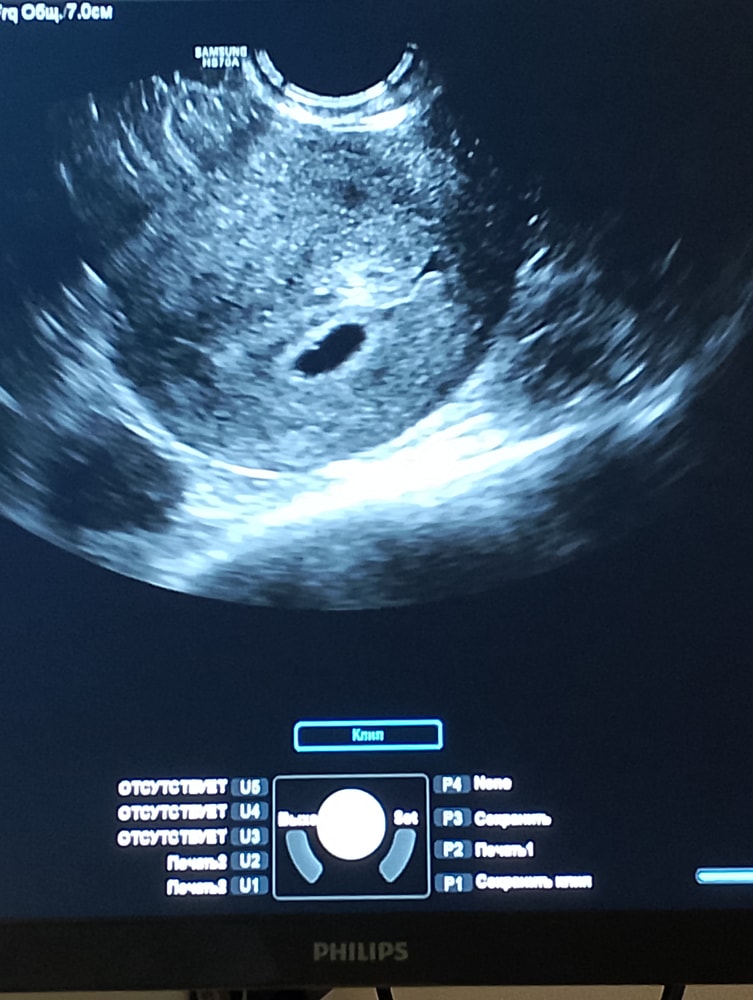

Сходила на Узи для подтверждения маточной беременности

Плодное яйцо -6 мм, по-моему маленькое..

ЖМ пока нет , это нормально или нет? (